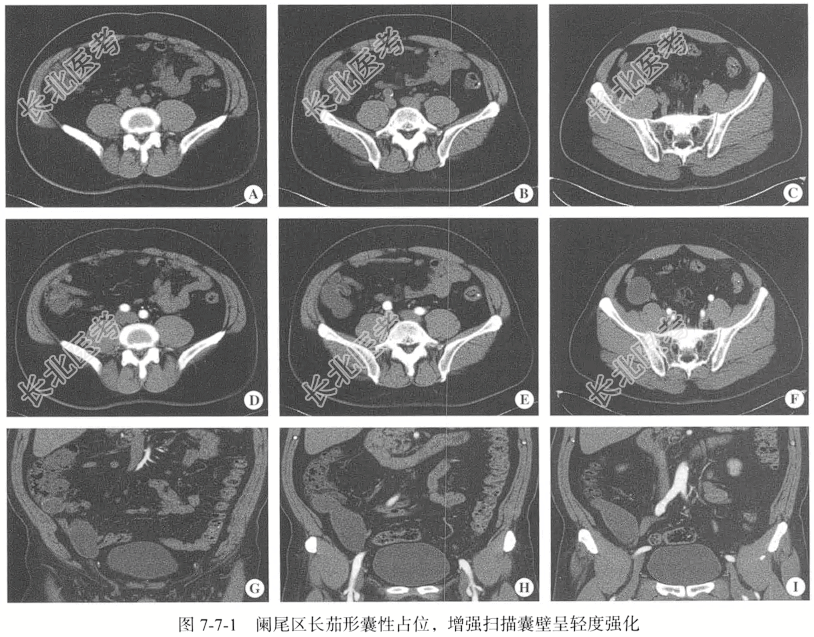

- [材料题] 【临床病史】男性,51岁。右下腹疼痛1月余,超声提示右下腹肿块。

【腹部CT检查】行腹盆腔平扫及双期增强扫描。扫描范围自膈顶至耻骨联合下缘。CT扫描参数:层厚5.00mm,层间距5.00mm,螺距0.984,最大管电压均为120kV,电流使用智能毫安调节,球管旋转0.8秒/圈。重建参数:以标准算法将原始图像以1.25mm层厚、1.25mm间隔重建;以3.5~4.5ml/s的流率静脉团注(剂量1.5ml/kg)非离子型对比剂,分别延迟20~25秒、45~55秒行动脉期及门静脉期扫描。

【影像图片】见图7-7-1。

【手术所见】腹腔内有约10.00ml淡黄色液体渗出,阑尾位于盲肠后位,长约6.00cm,浆膜增厚,呈慢性阑尾炎表现,阑尾周围粘连。

【病理所见】肉眼所见阑尾囊壁样组织一块,大小约为7.50cm×6.00cm×1.00cm,囊壁厚0.20~0.40cm,表面呈灰红色,内壁呈灰白色,质中,上附黏液样物,另见黏液样物一堆,大小约为3.00cm×2.00cm×1.00cm(图7-7-2)。

【病理诊断】(阑尾)形态符合低级别阑尾黏液性肿瘤,伴局灶肌层内钙化。